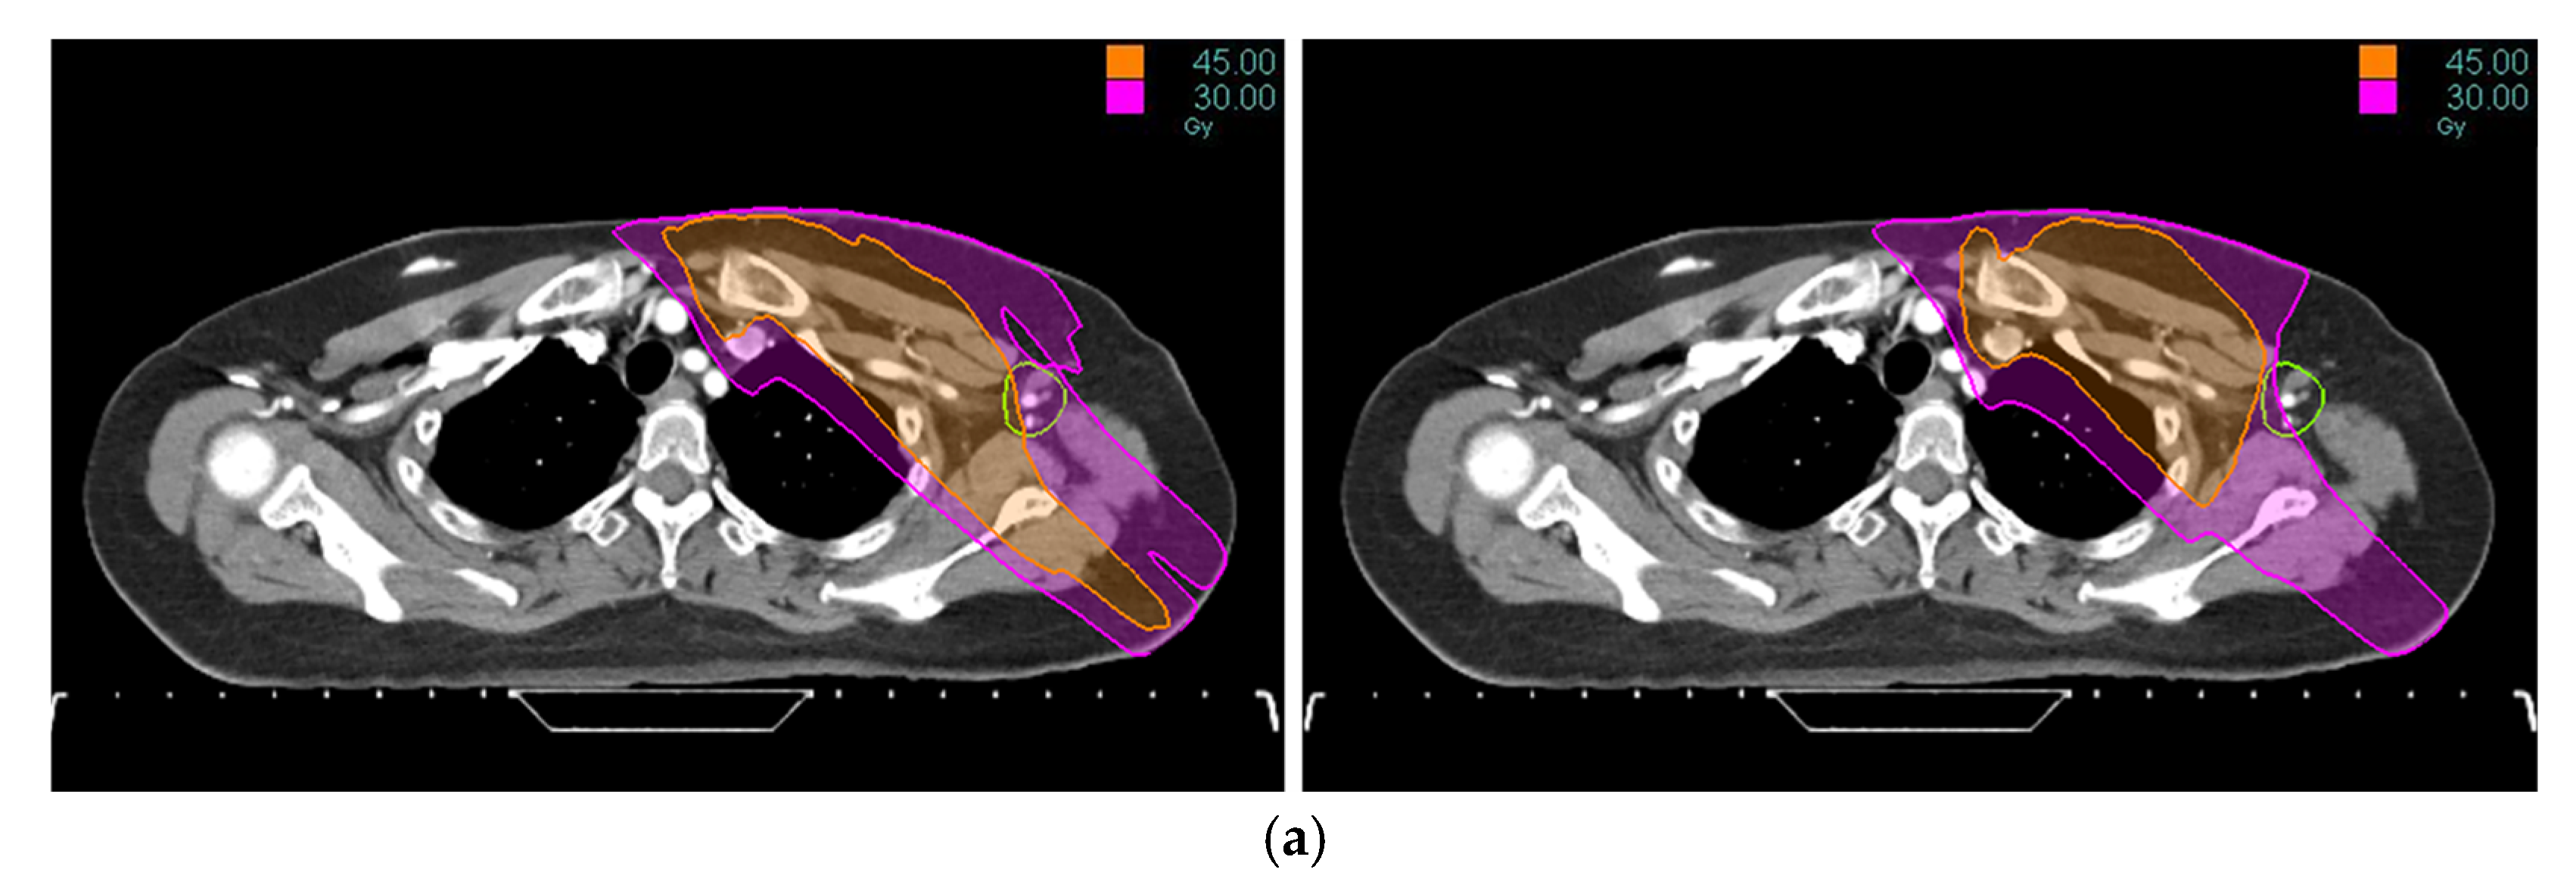

Tomotherapy plan images along with the DVH of a typical patient is illustrated in Figure 1 and Figure 2. The newly generated plans, successfully optimized to meet all standard dose-volume constraints for both target volumes and standard OARs, achieved significant sparing of the ALTJ without compromising the dose received by other critical OARs.

Figure 1. Tomotherapy plan image of a typical patient: (a) axial view, (b) coronal view. The contoured ALTJ (green) is shown, and the dose distributions with isodose lines (30 and 45 Gy) compared between conventional (left) vs. study plan (right).